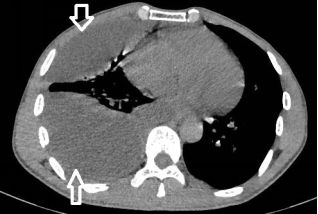

下面这种胸水,看着也挺多,但是,也是反重力的存在:貌似水往低处流!

在胸腔镜下,是“蜘蛛网+蜂窝状”般的变态存在。

看看你的胸腔积液和人家的胸腔积液,你的引流管和别人的引流管!

对于包裹性积液,胸腔积液粘稠或分隔形成,B超下的表现,如下图: